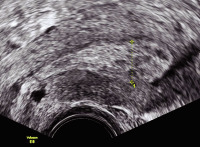

Tipps und Tricks im Gyn-Ultraschall: Das prämenstruelle und das menstruelle Endometrium

Journal für Gynäkologische Endokrinologie 2013; 7 (3) (Ausgabe für Österreich): 24-25 Journal für Gynäkologische Endokrinologie 2013; 7 (3) (Ausgabe für Schweiz): 33-34 Volltext (PDF) Abbildungen